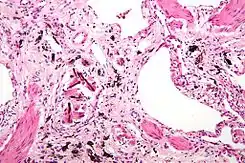

![]() Micrografía de asbestosis que muestra los cuerpos ferruginosos característicos y marcada fibrosis intersticial (o cicatrización). Tinción de H & E. | ||

El amianto es una sustancia inorgánica que al acumularse de forma progresiva y continuada produce destrucción y posteriormente cicatrices pulmonares crónicas debido a la incapacidad de las células de defensa pulmonar (macrofagos) de digerir y eliminar adecuadamente este material inorgánico. Estas cicatrices impiden el normal funcionamiento pulmonar (disminución de la expansión pulmonar por fibrosis, intercambio gaseoso), lo que explica los síntomas de la enfermedad.

Se produce así una neumoconiosis caracterizada por una fibrosis pulmonar (enfermedad pulmonar intersticial). Está asociada a mesotelioma y carcinoma broncogénico.